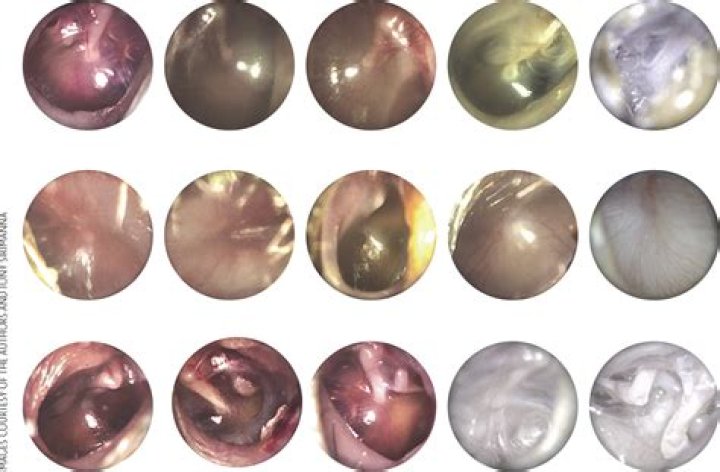

How is ome diagnosed?

A test called tympanometry is an accurate tool for diagnosing OME. The results of this test can help tell the amount and thickness of the fluid. The fluid in the middle ear can be accurately detected with: Acoustic otoscope.